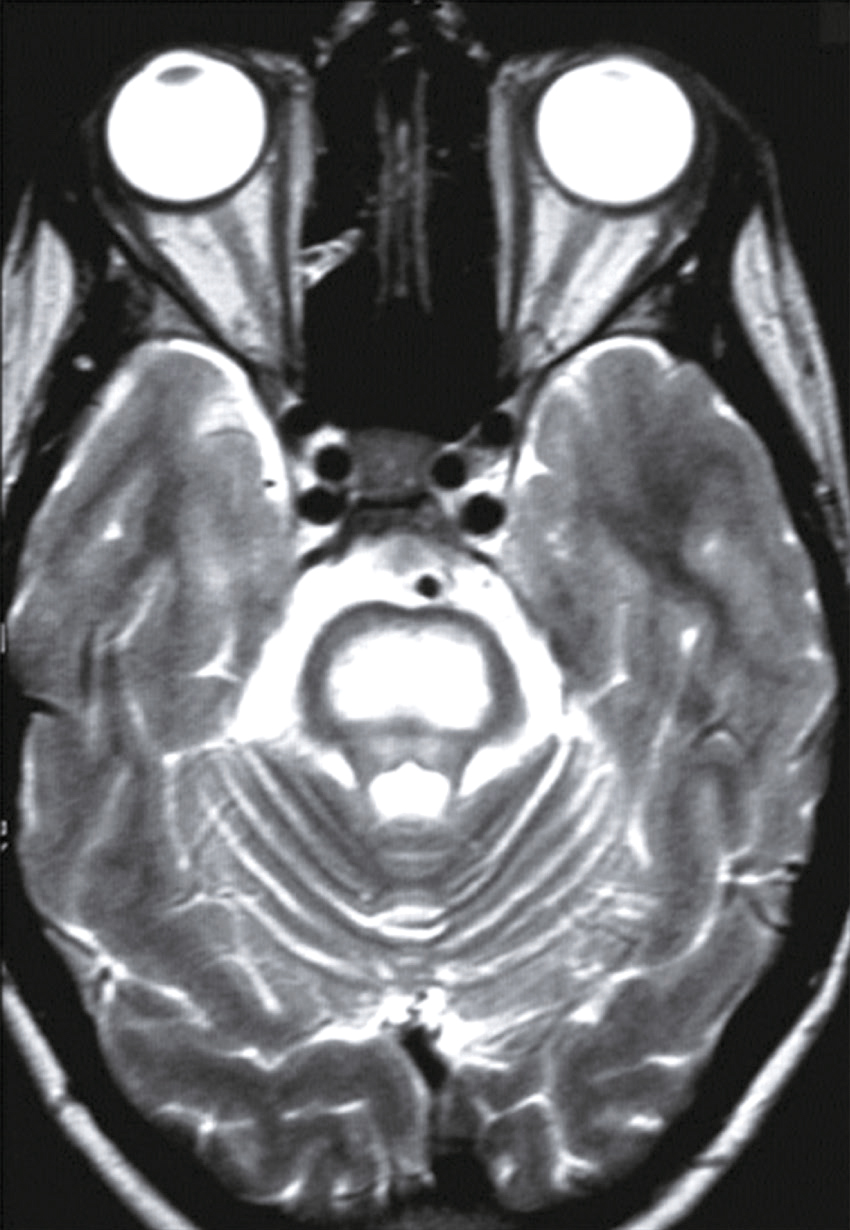

Vous débutez un traitement par benzodiazépine, vitaminothérapie B1, B6, PP, réhydratation par sérum salé et immunoglobulines polyvalentes intraveineuses associées à une héparine de bas poids moléculaire à dose isocoagulante. Le lendemain matin, le patient s’est aggravé d’un point de vue clinique. Il n’a plus d’hallucination visuelle mais il présente maintenant une tétraparésie évaluée à 3/5 avec ataxie des quatre membres, une dysarthrie, des troubles de la déglutition, et une ophtalmoplégie bilatérale. Un bilan biologique a été prélevé avant votre arrivée : numération formule sanguine : Hb : 13,8 g/dL, leucocytes : 8 600/ mm3, plaquettes : 332 000/mm3, ionogramme sanguin : Na+ : 142 mmol/L, K+ : 4,2 mmol/L, clairance de la créatininémie : 92 mL/min, glycémie : 5,8 mmol/L, transaminases, phosphatases alcalines, bilirubines et γ-GT normales, CRP : 3 mg/L.

Une IRM cérébrale a été également réalisée (fig. 31.4). Quelle est la séquence présentée ?

- A T1

- B écho de gradient

- C T2

- D T2/FLAIR

- E diffusion